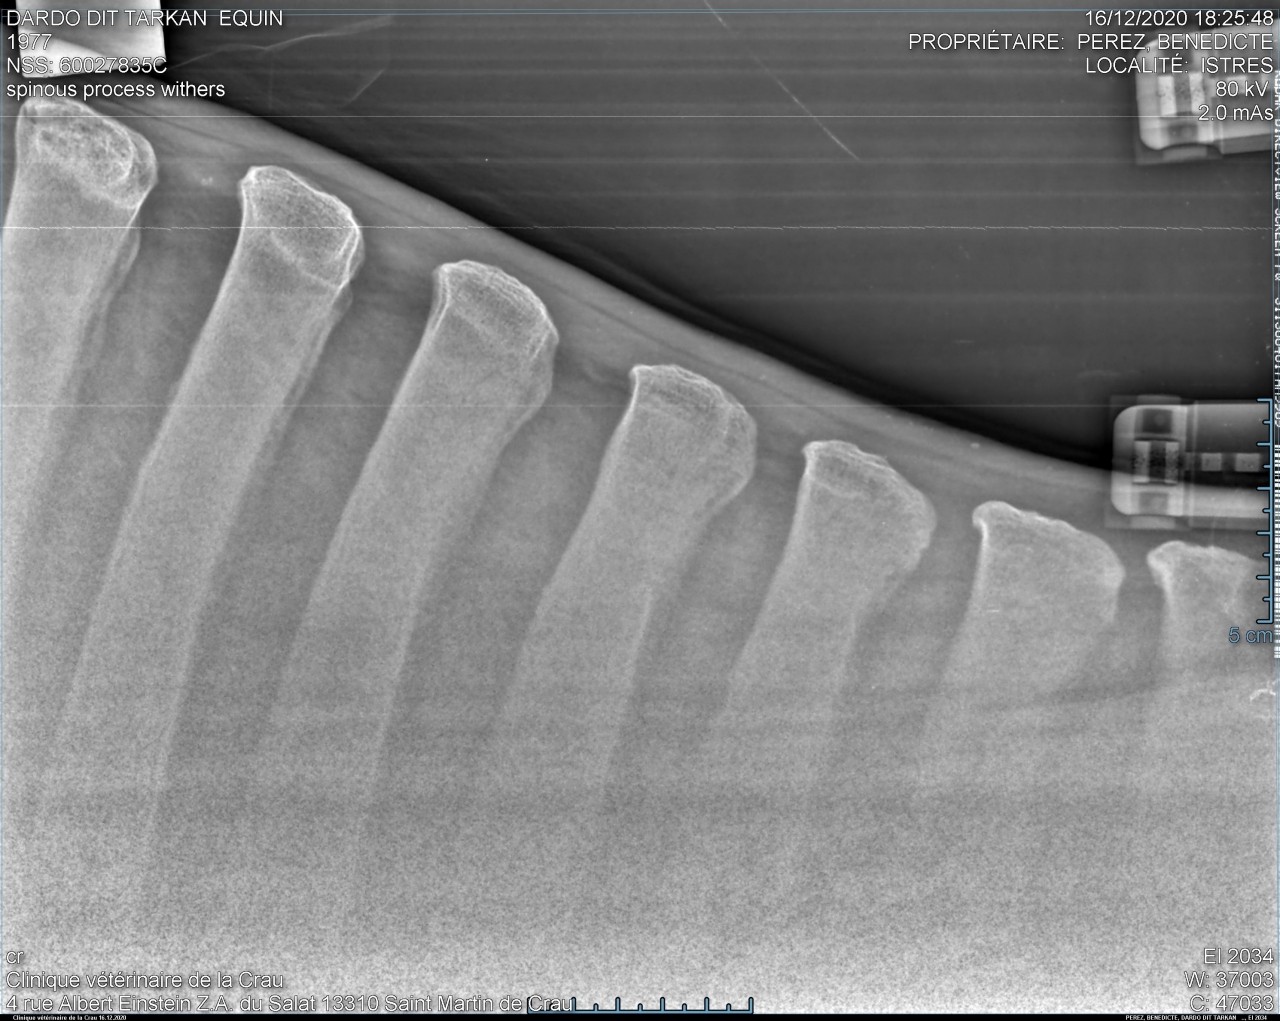

| Dire merci | bon... sans suspens aucun voilà les radios de Takhan : garrot très bien : ![]() ![]() T15/16 : la cata ![]() ![]() puis les lombaires.... acceptable mais pas génial : ![]() ![]() Je le savais mais ça fait un choc tout de meme... Je débriefe avec la véto aujourd'hui pour savoir ce qu'on fait, méso, laser? bref on va voir... Il est très très contracturé sur le dos donc déjà on va traiter ça avec mon osteo qui est aussi shiatsu girl et masseuse. Ça fait chier quand meme... |

| Dire merci | Alors oui dawa , sur les radios du garrot, tu vois que les vertèbres sont bien écartées, l'os parait visuellement "propre". Tout va bien. Sur les lombaires c'est un gros plan sur le haut des vertèbres et tu vois que l'espacement entre les vertèbres est mince mais existant. Rien ne se touche. On considère que c'est problématique quand l'espacement est en dessous de 4mm. Pour le dos, donc T15/T16 (sous mes fesses pour faire simple), tu vois que les vertèbres se touchent, et en plus, sur un coté de la radio tu vois une petite tache blanche entre les 2 vertèbres c'est ce qu'on appelle le chevauchement. Y pas encore de pont osseux donc on peut pas dire qu'il soit soudé encore.Pas complètement quoi. |